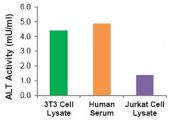

Trong bài viết này tìm hiểu về bệnh Alanine aminotransferase (ALT/GPT). Nếu như bạn có vô tình mắc phải bệnh này thì những thông tin trong đây mà eLib sẽ giúp bạn phát hiện được và chữa trị một cách hiệu quả nhé!